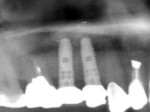

術前レントゲン

抜歯を行う。折れていた位置がかなり深い位置であるのがわかる。

埋入直後のレントゲン。上部に見えるのは抜いた歯を利用して両どなりの歯に接着して一時的に使えるようにした。